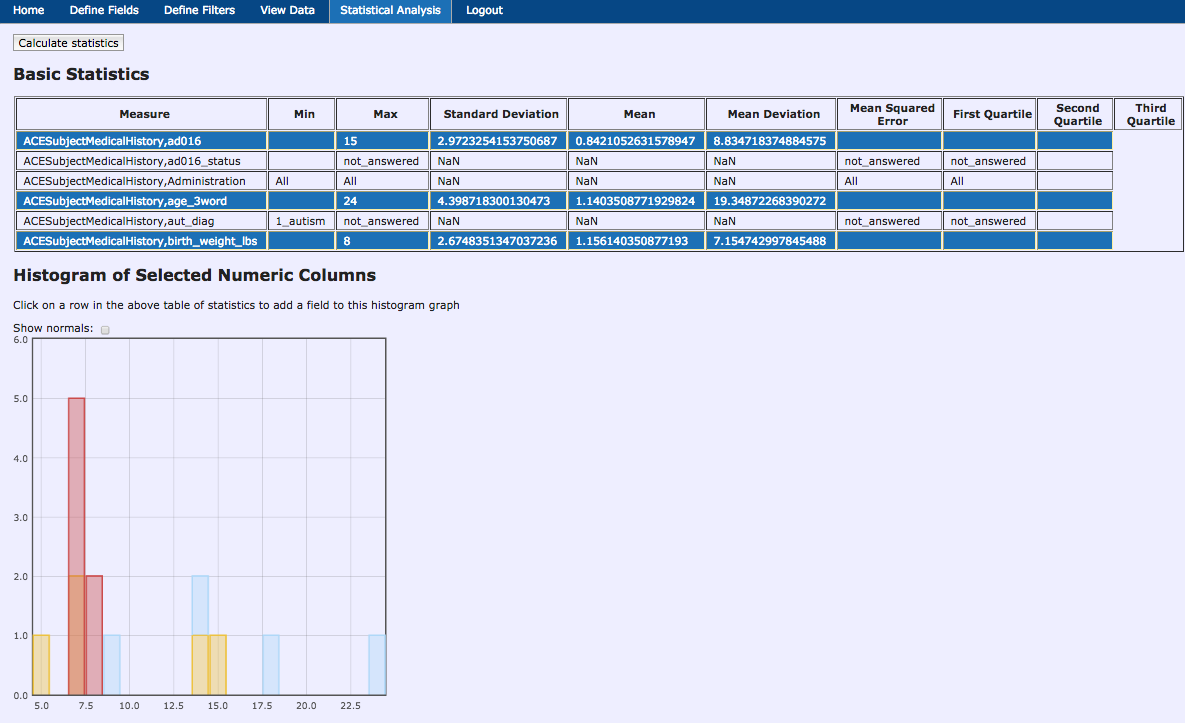

Data Querying Tool

Data Querying Tool - Results

Data Querying Tool - Statistics